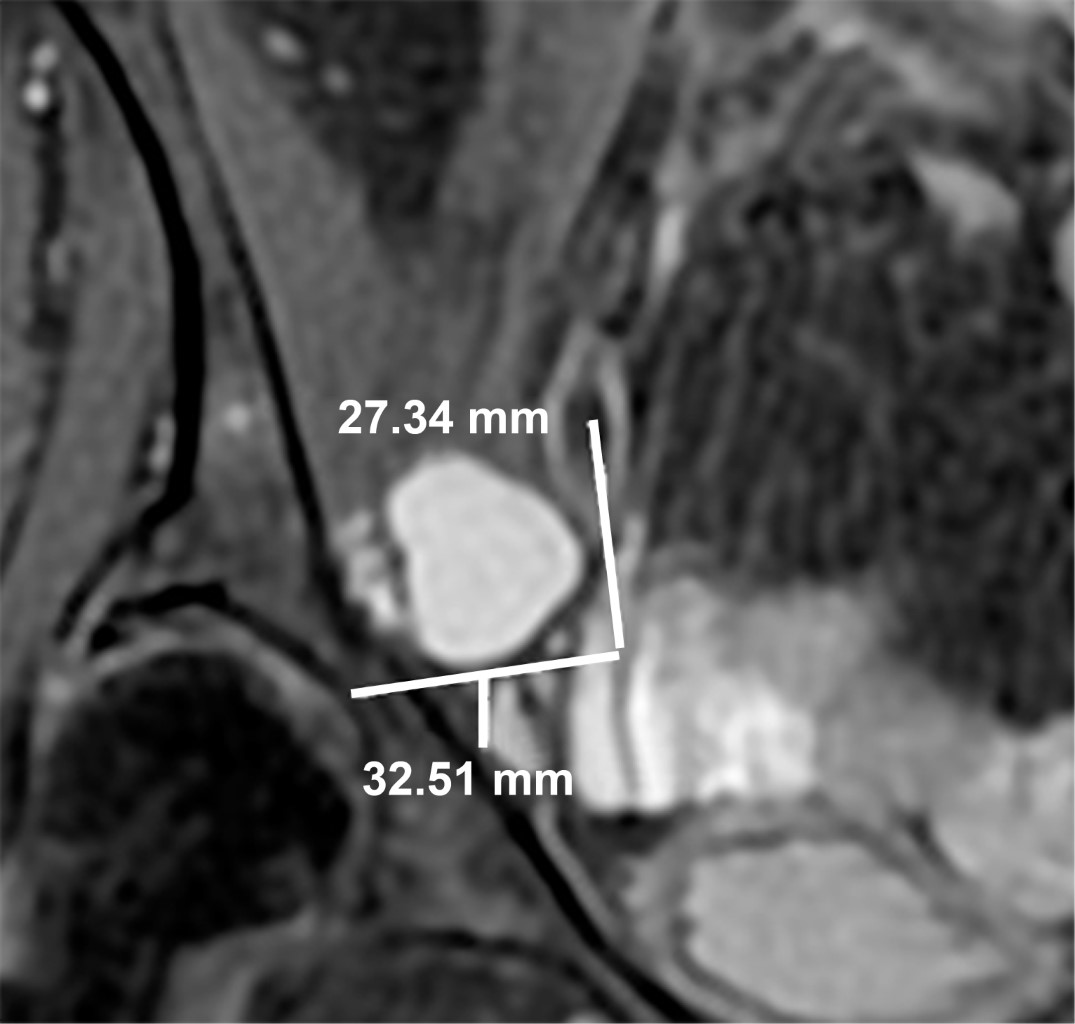

Se le realizó estudio de resonancia magnética de cadera derecha en secuencias potenciadas en T1, T2 y saturación grasa en los planos coronal, sagital y axial. Se observó fractura del labrum acetabular derecho con imagen sacular, de aspecto pediculado multilobulado, de contenido líquido, mide en el plano sagital de 42 × 15 mm, así como imagen circular bien delimitada que continúa hacia la porción superior y por debajo del músculo psoas, con diámetros en el plano sagital de 28 × 22 mm (Figura 1), en el plano coronal mide 32 × 27 cm (Figura 2) y en el axial 32 × 23 mm (Figura 3), sugestiva de quiste paralabral. Signos discretos de coxartrosis bilateral e hipotrofia de los músculos de la región glútea del lado derecho en comparación con el lado izquierdo.

Figura 3